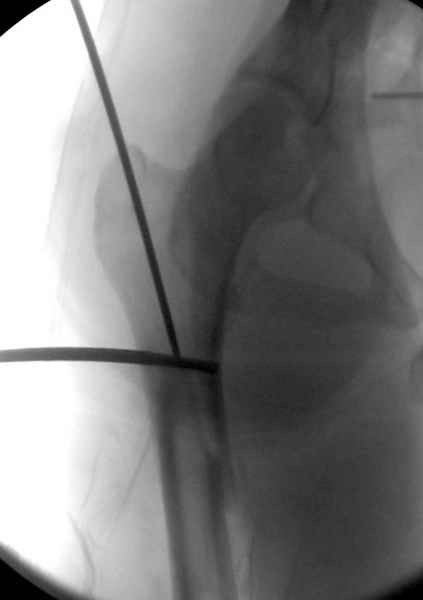

Как раз недавно у меня был примерный случай: больному 36 лет, поступил ночью, травма в результате мотоциклетной аварии, кроме чрезвертельного и спирального перелома левого бедра имеется переломы костей предплечья с этой же стороны. Скелетное вытяжение, а на следующий день больной про оперирован на ортопедическом столе с дистракцией. Чтобы не расколоть чрезвертельный перелом провели временную спицу ближе к переднему кортексу, из малого разреза костодержатель для репозиции, а фиксацию провели антиградным штифтом. Этапы операции на снимках.

Второй случай тоже репозиция из малого доступа, больному 19 лет, множественные огнестрельные повреждениия конечностей, живота и черепа, правая конечность холодная, без пульсации. Ортопедический диагноз: огнестрельный перелом правого бедра. При срочной ангиографии повреждения сосудов не подтвердилось, конечность из-за ургентности состояния больного зафиксирована временным наружным фиксатором и больной оставлен на операционном столе для срочной лапаротомии хирургической службой.

Больной долго оставался нестабильным, только на 14 день удалось заменить на антеградный интромедуллярный штифт TFN (trochanteric femoral nail) SmithNephew. После неудачной попытки закрытой репозиции, несмотря на использование "joystick", проксимальный стержень от

наружного фиксатора, (перелом начал срастаться) репозицию провели из малого доступа, затем остальные этапы операции.

Случай был представлен из-за того, что больного оперировали после наружной фиксации и был риск инфекцирования через места проведения стержней (на снимках), прошло больше 3 месяцев, выписан из амбулаторной службы из-за отсутсвия надобности дальнейшего наблюдения.